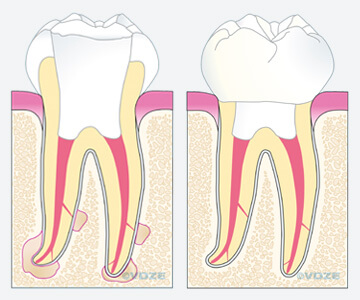

Haben sich an einem Zahn Bakterien im Sinne einer Karies angesiedelt, so besteht die Möglichkeit, dass der Zahnnerv infiziert wird (Bild Mitte). Als Folge dessen reagiert der Zahnnerv mit einer Entzündung, die zu einem Absterben des Nervens führen kann. Die Bakterien können sich dann im Wurzelkanalsystem innerhalb des abgestorbenen Nervgewebes vermehren und im Kieferknochen eine Entzündung hervorrufen. Diese Entzündung kann zu einer häufig zu beobachtenden Aufklopfempfindlichkeit des erkrankten Zahnes und einem Anschwellen der betroffenen Region führen. In seltenen Fällen können aber auch Unfälle oder zahnärztliche Behandlungen Ursache für die Erkrankung eines Zahnnervs sein.

Ziel dieser Maßnahmen ist es, das ursprüngliche Kanalsystem möglichst in einen keimarmen und sauberen Zustand zu bringen. Dieses hört sich zunächst sehr einfach an, doch bergen z. B. kleine Seitenkanäle die Gefahr einer möglichen Reinfektion (siehe Pfeile in Bild links und rechts). Auch diese müssen sorgfältig gereinigt und möglichst perfekt aufgefüllt werden. Aus diesem Grund nehmen wir uns für Ihren Zahn die entsprechende Zeit, um die oben beschriebene chemomechanische Desinfektion durchzuführen.

Nach vollständiger Instrumentation und Desinfektion des Wurzelkanalsystems muss das entstandene Hohlraumsystem mit einem Füllmaterial bakteriendicht versiegelt werden. Optimale Ergebnisse lassen sich mit der sogenannten dreidimensionalen thermoplastischen Obturation erreichen: Eine Art Gummi wird in erwärmten, fließfähigem Zustand in die Kanäle eingebracht und durch nachfolgender Kompression in die Hohlräume hineingepresst. Anschließend wird der Zahn mit einem stabilen Aufbau fest verschlossen (Bild links). Dieser dient auch als Vorbereitung für eine spätere eventuell notwendige Überkronung (Bild rechts). In den folgenden Monaten heilt die Entzündung um die Wurzelspitzen des jeweiligen Zahnes ab, der zuvor geschwundene Knochen regeneriert sich wieder (Fallbeispiel im nächsten Abschnitt)